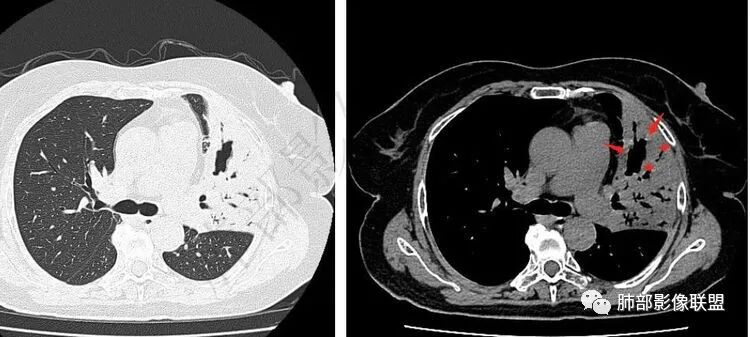

壁连续软骨破坏不明显可见不规则空洞,内壁光滑、腔内干净,远端支气管显示清楚病灶收缩明显左下叶见多发边界清楚结节、树芽征

糖尿病,病史半月,症状逍遥空洞特点、支气管特点、树芽征,支持结核不除外恶性肿瘤傅昌瑜:

4.左肺下叶多发结节影及条索影,密度不均,边界较清楚,可见树芽征。

5.纵隔见轻度增大淋巴结,较密实。

左肺下叶多发结节影、条索影、树芽征等具有相当明显的提示意义—符合继发性肺结核。

D-二聚体升高,肺动脉成像等明确患者肺栓塞的存在!